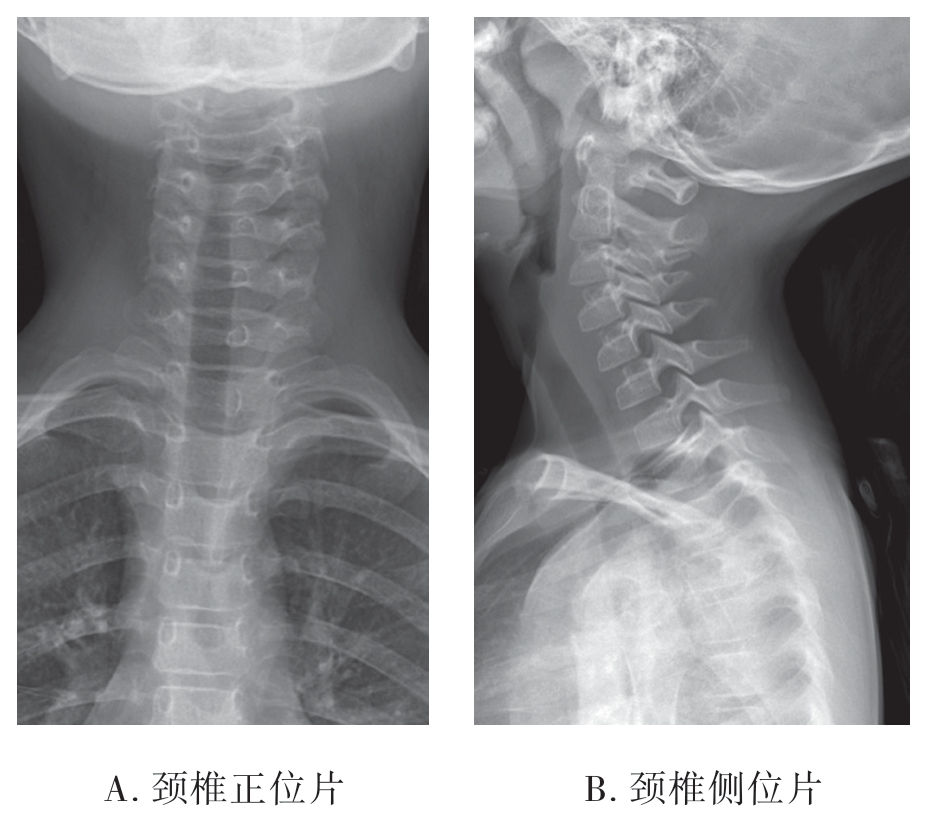

婴儿椎体侧位像为横卵圆形,前后有横“V”字形透亮线影,椎体与椎弓分离。1~2岁椎体渐成扁方形,上下径明显短于横径,边缘钝圆;学龄前大致为长方形,角为钝角;6~9岁椎体的角逐渐变为直角;约12岁椎体上下面的环状软骨开始骨化,出现环状骨骺,因椎体前缘上下角处的环状软骨较厚,侧位上呈三角形或条状骨化影;15岁时环状骨骺开始与椎体联合;至25岁完全联合(图7-2-1)。

图7-2-1 儿童颈椎X线正侧位片